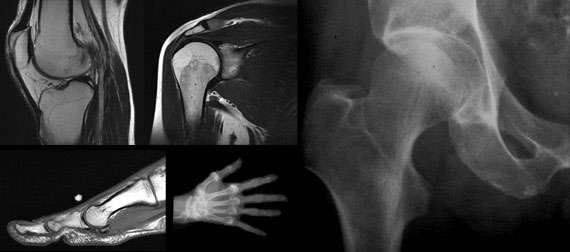

Musculoskeletal Imaging

Musculoskeletal Radiology performs the full range of musculoskeletal imaging using a variety of modalities, including general radiography, CT, MRI, and arthrography. Radiologists in this subspecialty also assist in the interpretation of musculoskeletal radionuclide bone scans, read in conjunction with a nuclear medicine physician.